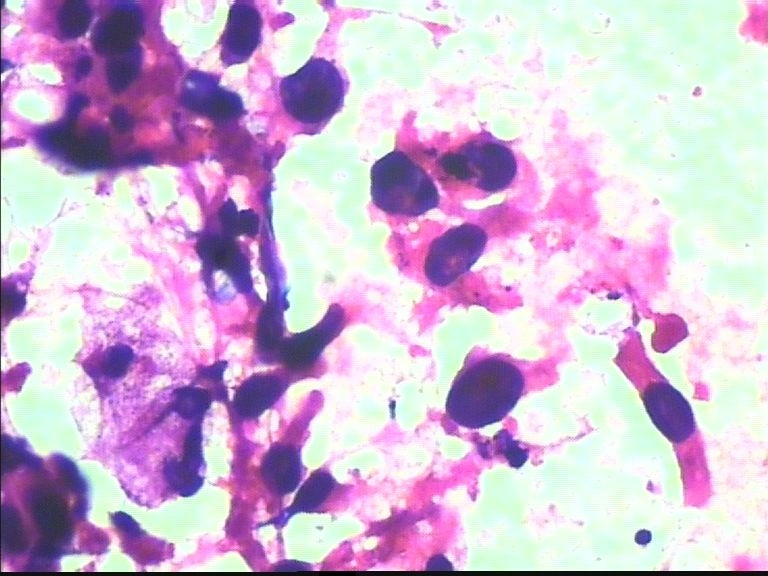

38岁 乳腺肿瘤 女

• 38岁 乳腺肿瘤 女图1

图1

考虑癌:图18细胞核形式不规则,染色质粗块状,可见核仁.

乳腺癌

乳腺癌。

浸润导管癌

好像重复了。浸润性导管 癌。

从所给图看恶性是没什么问题!染色有点过,染色质结构欠清晰;关于细胞学判断浸润的问题我想应综合来判断,如单个细胞的异形性,细胞整体弥散情况,细胞微粒结构以及间质成分等等,个人的认识也起到一定因素,细针穿刺中最常规用的还是--导管癌。